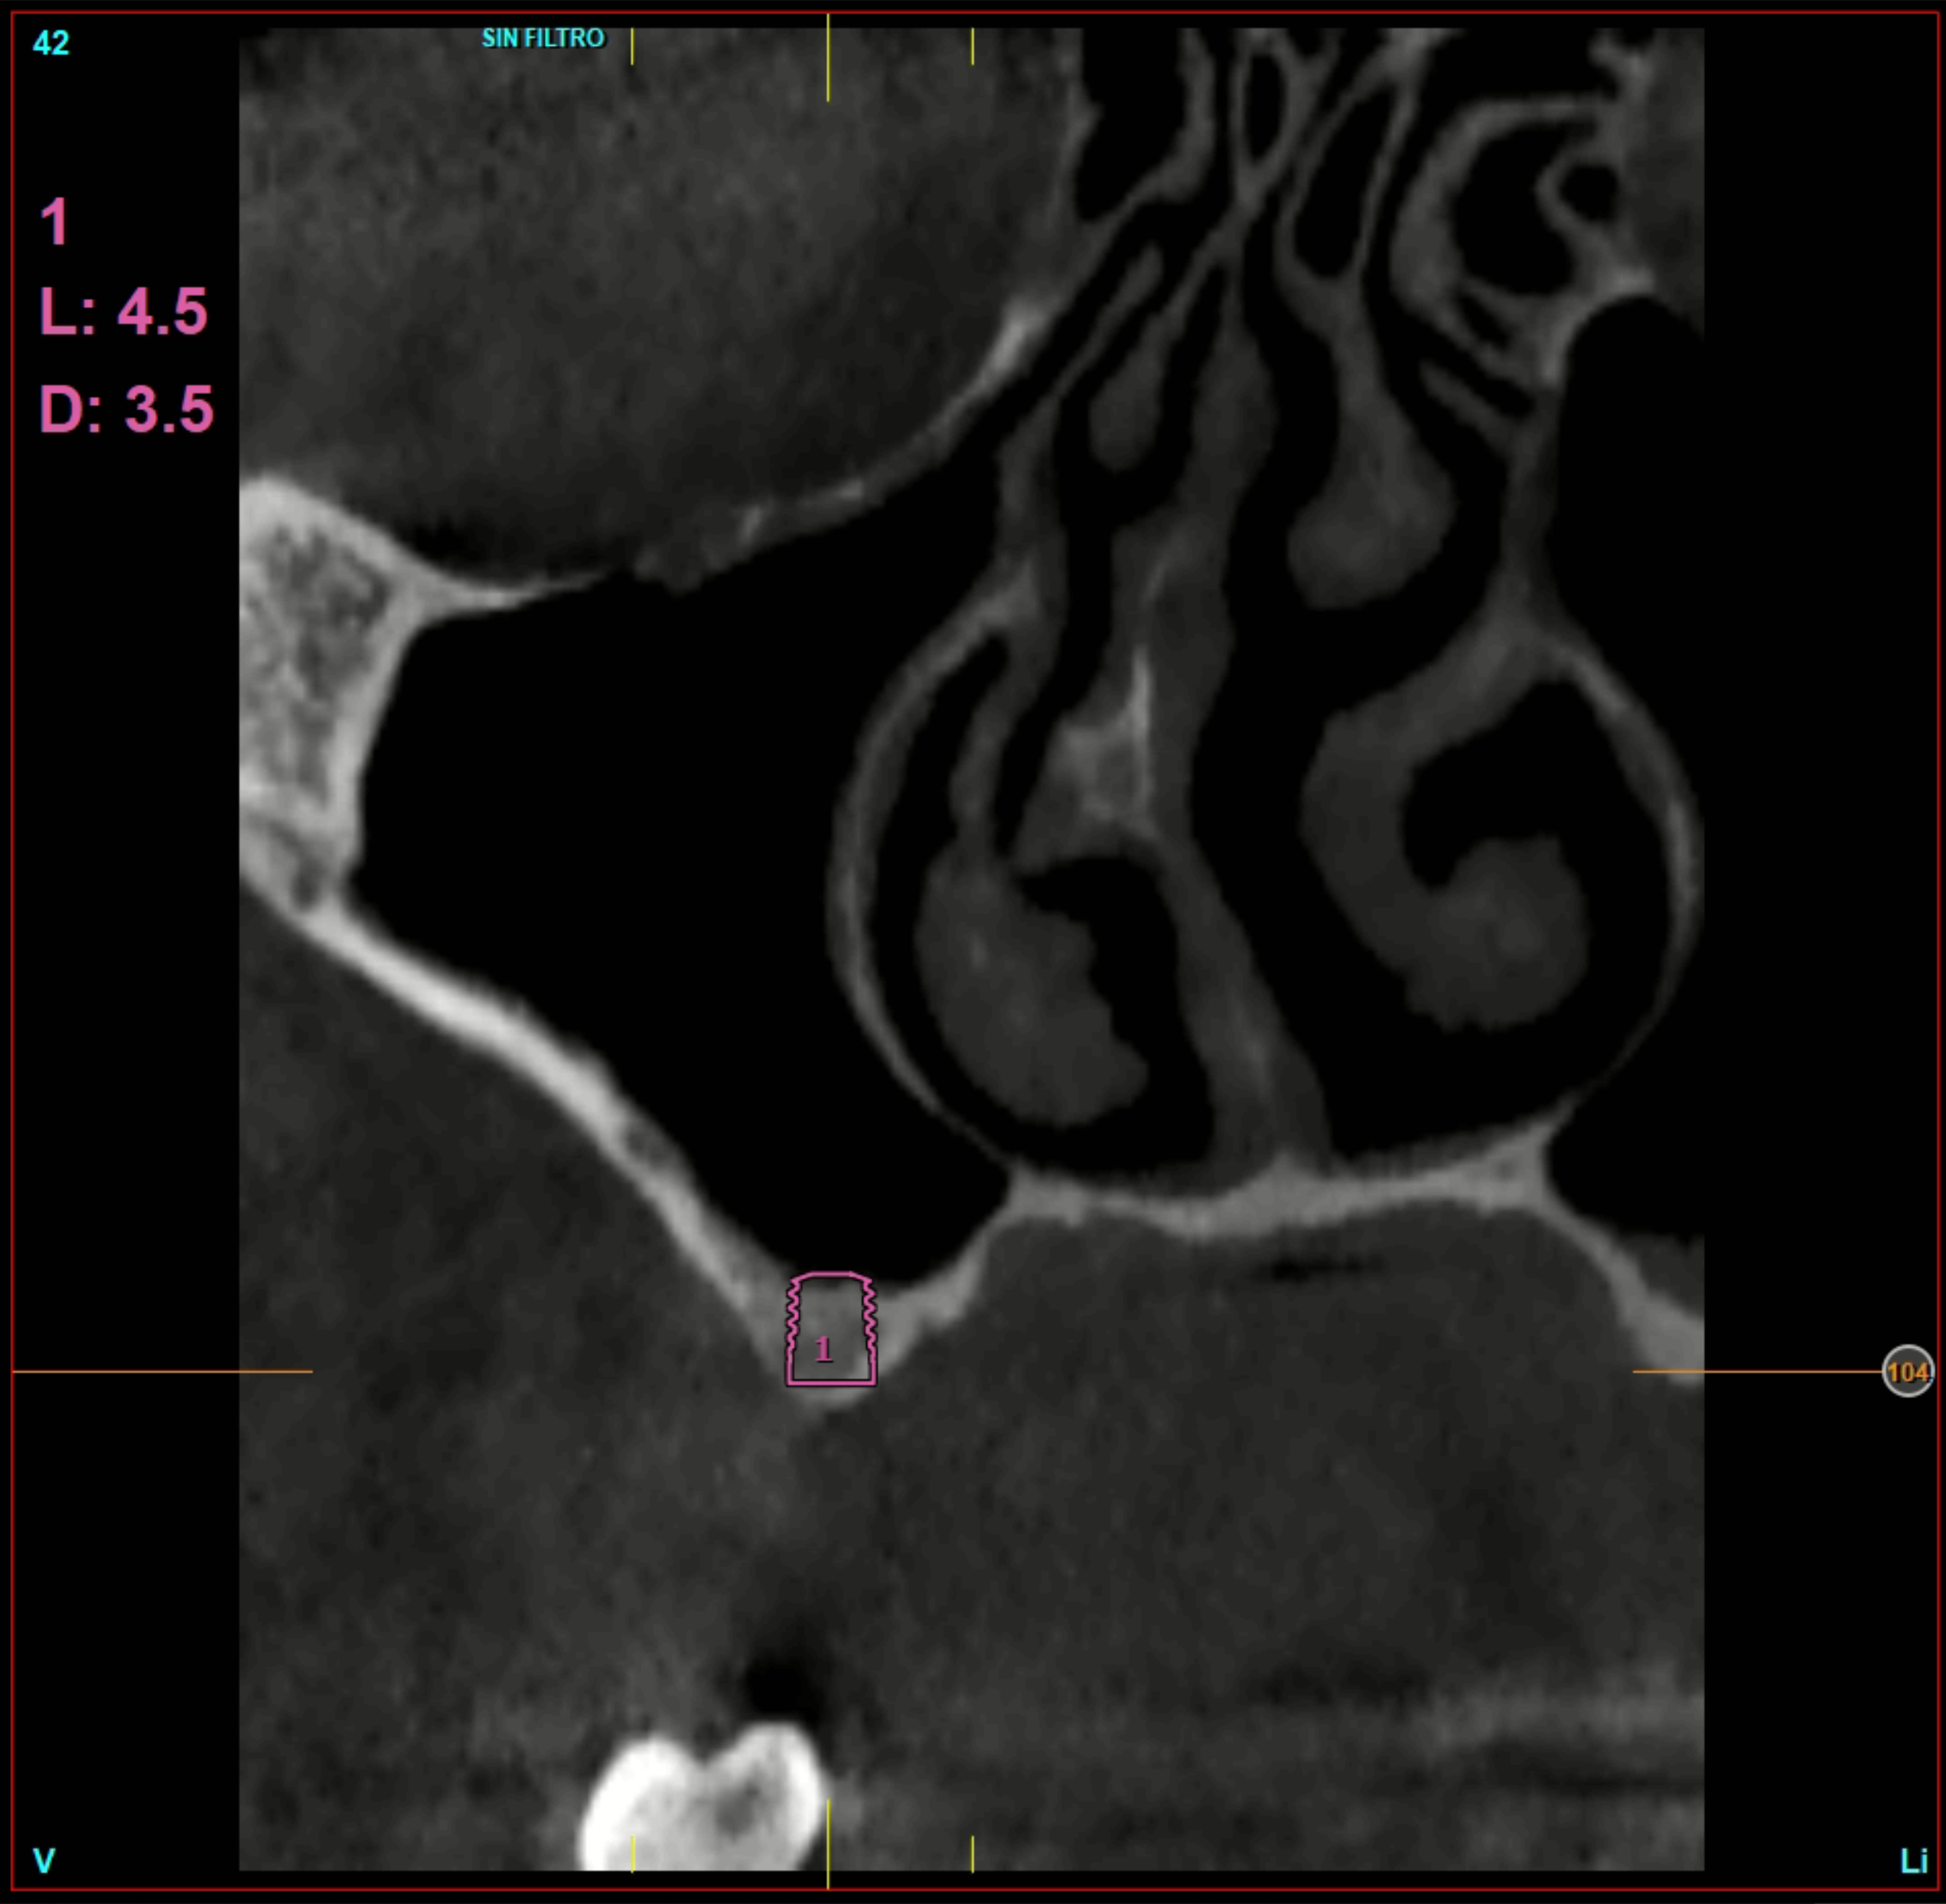

È stata effettuata una revisione retrospettiva di tutti i casi nei quali sono stati inseriti impianti di 4,5 mm di lunghezza sottoposti a protocollo di carico immediato. I trattamenti sono stati eseguiti in un’unica clinica di Vitoria (Spagna) negli anni 2020 e 2021. Nell’ambito dello studio preoperatorio, tutti i pazienti sono stati valutati mediante esame clinico, modelli diagnostici e CBCT (Cone Beam), successivamente analizzati con un software di pianificazione dedicato (BTI-Scan III). Al fine di definire con precisione la futura riabilitazione, è stato eseguito un ceraggio diagnostico dal quale è stata realizzata una guida chirurgica personalizzata.

L’altezza media della cresta ossea residua era di 5,11 ± 1,06 mm, mentre la densità ossea media nelle sedi implantari era di 566,67 ± 349,48 HU. Il torque medio di inserimento degli impianti è stato di 34,71 ± 18,25 Ncm. L’analisi del torque in funzione della posizione implantare e del tipo di osso ha evidenziato un comportamento biomeccanico coerente con la densità ossea attesa per ciascuna regione anatomica. Gli impianti inseriti in osso di tipo I e II hanno generalmente raggiunto valori di torque più elevati, frequentemente compresi tra 40 e 60 Ncm, soprattutto nelle regioni posteriori (26, 27, 36 e 37). Al contrario, negli impianti inseriti in osso di tipo III e IV, i valori di torque tendevano a essere inferiori e più dispersi, oscillando prevalentemente tra 20 e 40 Ncm. Nonostante ciò, anche nei siti con qualità ossea inferiore, i valori ottenuti rientravano in intervalli clinicamente accettabili per consentire la stabilità primaria necessaria ai protocolli di carico immediato adottati nello studio. Nel Grafico 3 è riportata la distribuzione del torque in base alla sede anatomica e al tipo di osso.

In 19 impianti sono state eseguite procedure complementari contestualmente all’inserimento implantare: in due casi rigenerazione verticale con osso autologo da fresaggio associato a PRGF-Endoret; in 11 casi rialzo del seno mascellare transalveolare con osso autologo e PRGF-Endoret; in sei casi sovracorrezione vestibolare mediante osso autologo e PRGF-Endoret, associando uno strato di biomateriale (idrossiapatite bovina) per ridurre il riassorbimento volumetrico. Quattro impianti da 4,5 mm sono stati ferulizzati ad altri impianti della stessa lunghezza, per un totale di otto impianti ultra-corti ferulizzati tra loro, configurando ponti supportati da tre impianti. La protesizzazione definitiva è stata eseguita tra tre e nove mesi dopo il carico immediato. Le protesi definitive erano in metallo-ceramica nell’80,6% dei casi e in resina con struttura metallica nei restanti.

Al termine del follow-up, la perdita ossea crestale media è stata di 0,73 ± 0,18 mm in mesiale e di 0,85 ± 0,34 mm in distale. Alcuni casi clinici rappresentativi sono illustrati nelle Figure 2-10.